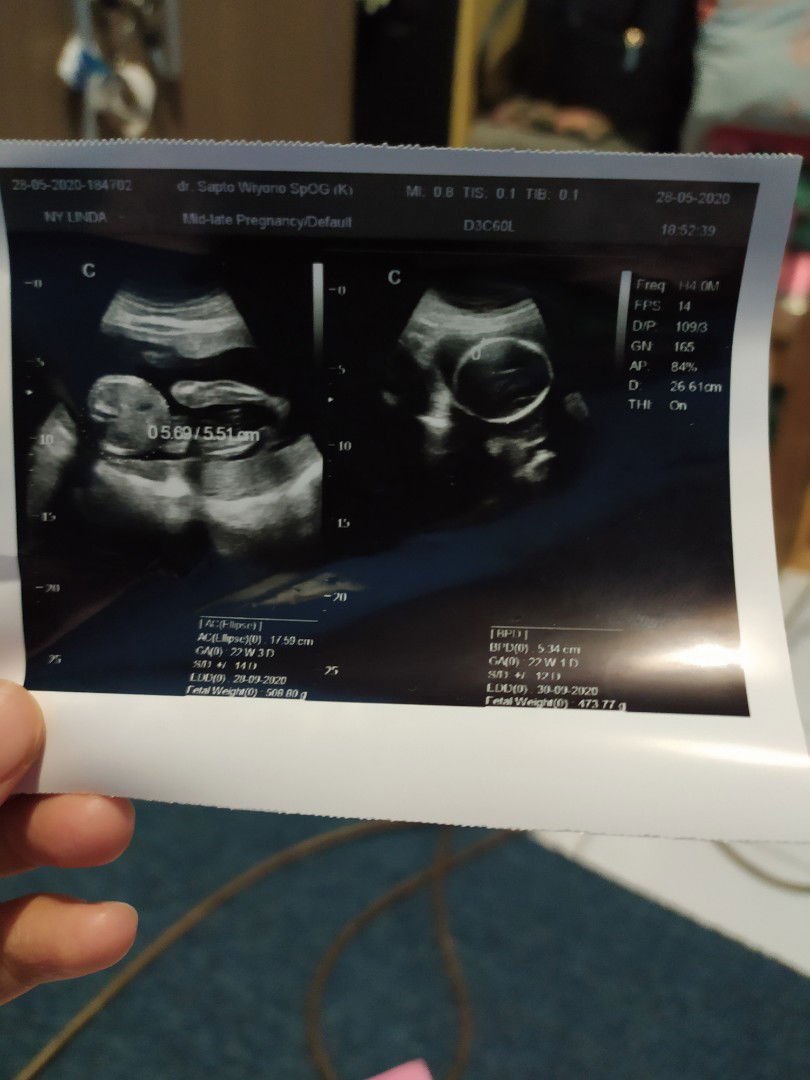

Tinggi Janin

Bun mohon informasinya, kalau dilihat dari hasil usg itu berati panjang janin sekitar 17,59 ya? Sementara kalau saya liat di app ini sama app yg satunya kalau janin 22w tingginya kisaran 22-27. Gimana ya Bun caranya agar bisa panjang janinnya?

Yg 17,59 itu AC ya bun? Itu bukannya ukuran lingkar perut ya? Kalau panjang seingetku CRL